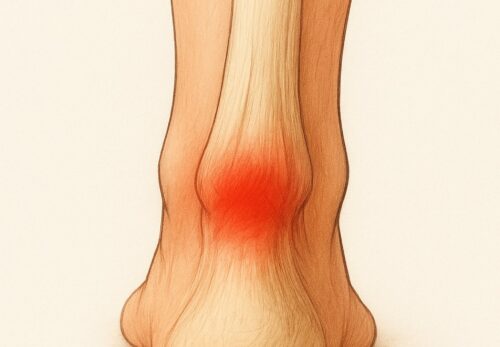

• 内側(牽引ストレス):靱帯や骨端部に強い引っ張り力 → 内側側副靱帯損傷、内側上顆炎、リトルリーグ肘

• 外側(圧迫ストレス):上腕骨小頭と橈骨頭の衝突 → 離断性骨軟骨炎(OCD)

• 後方(衝突ストレス):肘の伸展時に骨同士がぶつかる → 肘頭疲労骨折や後方インピンジメント

というように部位ごとに異なる障害が生じます。特に成長期は骨端線が弱いため、靱帯よりも骨にダメージが出やすいのが特徴です。